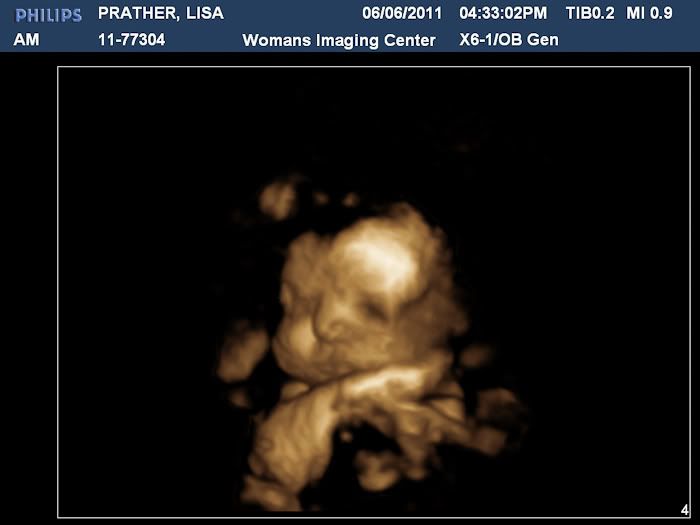

32 Week Ultrasound

We had an ultrasound today and got to see our baby boy! It was so wonderful to see him, but even better to find out that he is still perfect. He weighs 4 pounds and 11 ounces right now!

Here is his sweet face! I cried when I saw this. I think he is just precious!

Another shot of his face:

Here is a profile shot. You can see one hand up by his face. Both hands were up by his face pretty much the whole time until the end when we decided to stretch his legs by nearly kicking himself in the face!

The ultrasound technician said he had lots of hair. No wonder I've been having such bad heartburn.

We may have a future gymnast on our hands. His foot is right above his nose!

Then we got to see some in 3D, which were amazing!

Stephen thinks he has my nose and I think he has my cubby cheeks! We both think he is just adorable and can't wait to meet him!